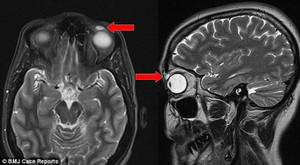

Chiếc kính áp tròng nằm yên vị suốt 28 năm trong mí mắt mà người phụ nữ đến từ Dundee, Scotland không hề hay biết.